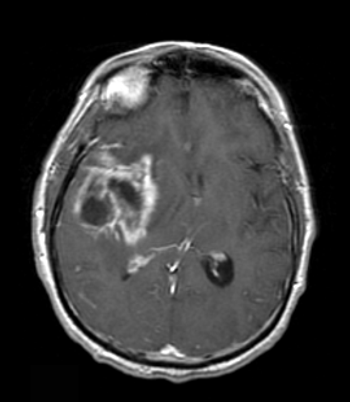

Positron emission tomography using [18]F-fluorothymidine as a tracer failed to distinguish true progression of glioblastoma from pseudoprogression in a small single-center study presented at the 2014 ASCO Annual Meeting.